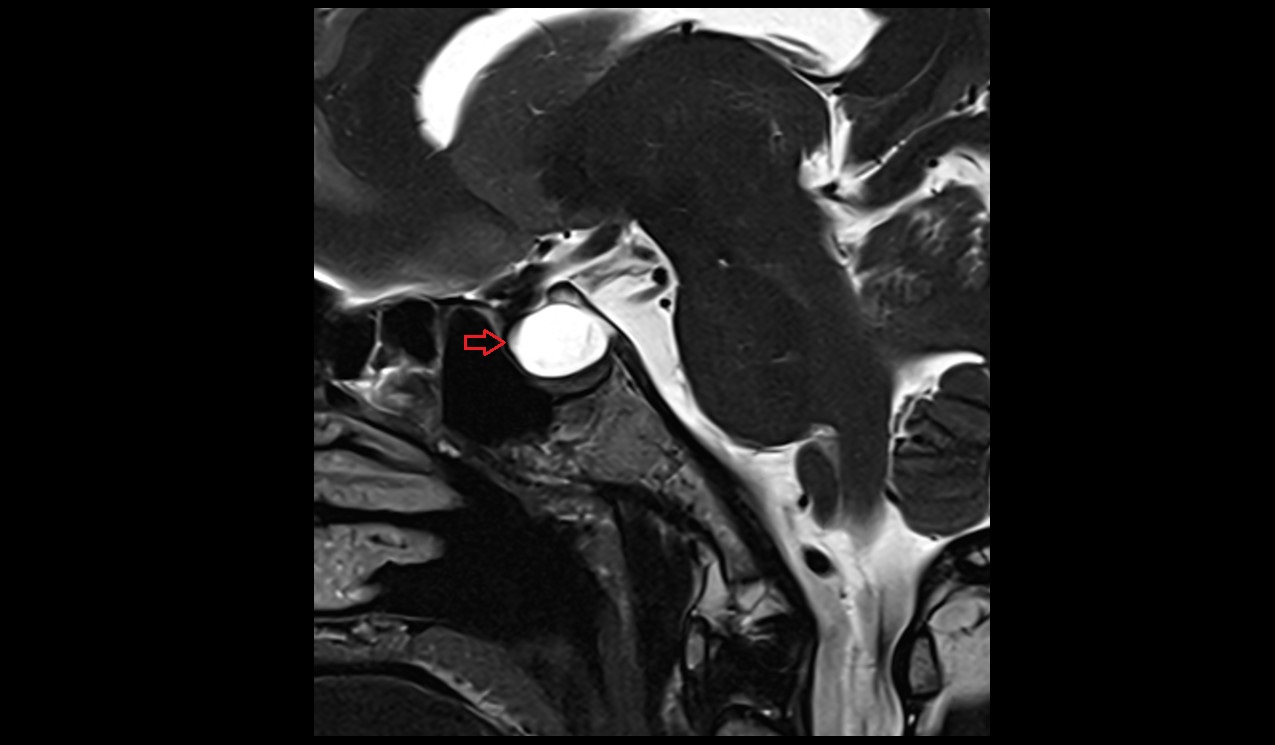

- Uterus

- Body of uterus

- Fundus of uterus

- Cervix of uterus

- Isthmus of uterus

- Endometrium of uterus

- Myometrium of uterus

- Perimetrium of uterus

- Junctional zone of uterus